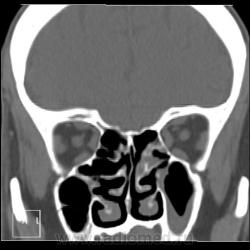

После пары менингитов на фоне синусита решили перебдеть. И вроде не зря... КТ: плотность содержимого в правой лобной пазухе 35-120 ед.Н. (мягкотканное с обызвествлением), в основной пазухе - 24 ед.Н (гнойной жидкости).

ну лобные можно засомневаться, а вот в правой гайморовой точно ведь есть затенение ее нижних отделов.

И пристеночный гайморит, и двусторонний этмоидит, и ринит, и односторонний сфеноидит, и фронтит, и очень тонкая костная пластинка между основанием передней черепной ямки и больной лобной пазухой - может быть реакция оболочек мозга...

По страшному снимку моему толком не видно, а вот на КТ множественные и разнообразные перегородки в пазухах видны хорошо. Я могу уверенно сказать только о следах жидкости в правой верхнечелюстной пазухе и субтотальном заполнении гомогенной жидкостью левой половины основной пазухи. Остальное, на мой взгляд, утолщение слизистой. Но на 100% утверждать не буду. В правой лобной я предполагаю (и только!) полипоз.

На 6 и 7 снимках... Справа затемнены передние ячейки решетчатых костей, слева - задние, слева процесс конечно интенсивнее.

хр.фронтит: справа с образованием обызвествленных полипообразных образований,слева- в виде утолщения слизистой оболочки. Решетчатый лабиринт клиновидной кости занят патологическим содержимым жидкостной плотности(?) с обеих сторон. Основная пазуха: справа - пристеночное утолщение слизистой, слева - тотальное заполнение. Определяется утолщение слизистой верхнечелюстных пазух, видимо воспалительного характера.